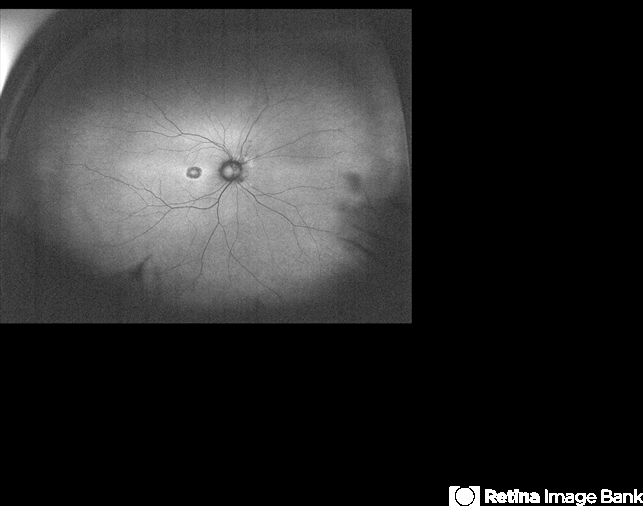

- cone dystrophy, macula, fundus autofluorescence (FAF), macula lesion, autofluorescence imaging

- Fundus autofluorescence of an 31-year-old male with cone dystrophy.